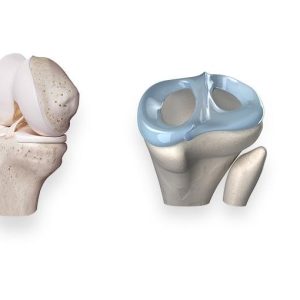

Хиймэл үе солих мэс засал (түнхний үе, өвдөг, мөрний үе 4,328 тохиолдол /мэс заслын хугацаа 1-2 цаг /эмнэлэгт 7-8 өдөр)

Төрөл бүрийн эмгэгээр үений гэмтэл авсан өвчтөнд хамгийн тохирсон хиймэл үе солих мэс засал.

Майга засах мэс засал(доод мөчдийн бэхэлгээ) 178 тохиолдол /мэс заслын хугацаа 1-2 цаг /эмнэлэгт 7-8 хоног

Мурийсан хөлийг засч, үений үрэвслээс үүссэн өвдөлтийг намдаах ажилбар